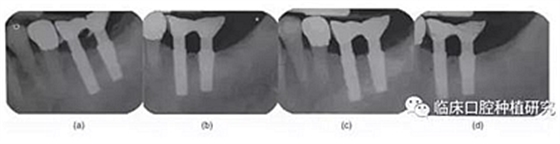

本研究的目的是評估種植體MicrothreadTM微螺紋結(jié)構(gòu)對維持種植體周邊緣骨水平的長期效果的作用。通過對同一種植系統(tǒng)(Astra)的兩種種植體(Astra Tech Single Tooth:帶頸部微螺紋和AstraTech TiOblast:不帶微螺紋)的三年前瞻性觀察研究,發(fā)現(xiàn)頸部微螺紋設(shè)計(jì)有助于維持種植體邊緣骨水平穩(wěn)定。